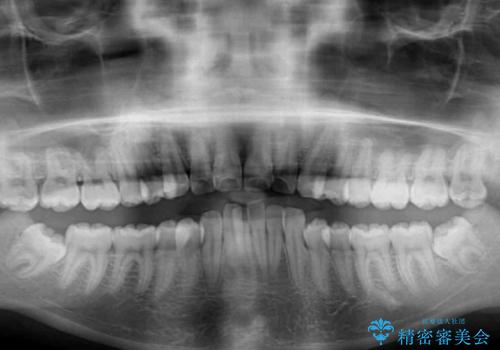

- 上下の出っ歯を気にして来院された患者様です。

口元を積極的に引っ込めるために、上下左右の第一小臼歯を4本抜歯することとしました。

途中で来院されない時期があったため、期間が長引き、更には磨き残しが多かったことで虫歯が多く発現してしまいました。

しっかりと通院するようになってからは順調に治療が進み、横顔の印象が変わるほどスッキリとした口元となりました。